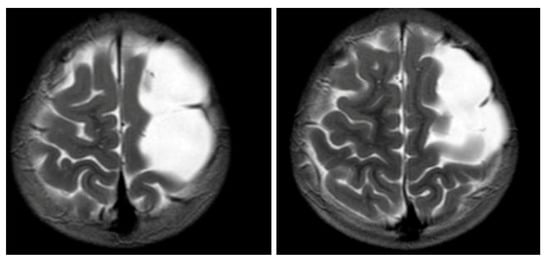

Figure 2. MRI T2WI, axial section in 2019. A very thin subdural hematoma is identified along the left convexity with mild edema noted in the subjacent perirolandic cortex. Decreased T2 signal is now identified within the cyst when compared to Figure 3 and Figure 4, which is suggestive of interval hemorrhage. These findings are consistent with a ruptured arachnoid cyst.

Figure 1 and Figure 2 reveal a change in signal of arachnoid cyst suggestive of interval hemorrhage with a thin subdural hematoma along its inferior aspect. Minimal edema in the subjacent Rolandic cortex was present. Given the patient’s stroke-like presentation, an MRA of head and neck was administered, which was found to be normal. The findings, with a comparison of the previous MRI of the patient at age 4 (Figure 3 and Figure 4), are consistent with a ruptured arachnoid cyst. No acute neurosurgical intervention was performed due to the absence of raised intracranial pressure and reduction of neurological symptoms. A routine EEG performed in the emergency department exhibited interictal epileptiform discharges over the left and right central–temporal region during drowsy and sleep states, suggestive of increased risk for partial seizures from these regions.

The patient received 500 mg levetiracetam twice daily for seizure prophylaxis. On day 2 of admission, a rapid-sequence MRI brain scan showed a stable thin subdural hematoma and a ruptured arachnoid cyst at the left frontoparietal vertex with the interval resolution of edema in the subjacent cortex. At discharge on day 3, the patient’s neurological exam remained normal without development of symptoms or signs related to acute intracranial hypertension. The patient maintained on 500 mg levetiracetam BID for seizure prophylaxis for three months. A rapid-sequence MRI brain scan at 2-week outpatient follow-up revealed a mild interval decrease in the size of left convexity subdural hematohygroma. He has had no return of rupture symptoms or concerns for seizures, including nocturnal seizures. He has occasional headaches, not sustained or requiring medication. The family express concerns regarding occasional anxiety and mild memory loss since hospitalization.